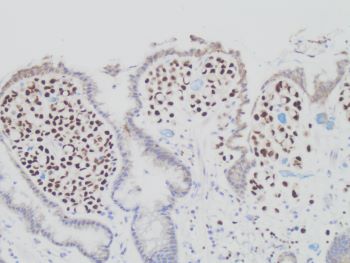

Given the lack of clinical history and the tumor cell location in the superficial gastric pits, the main differential diagnosis’ include diffuse-type gastric carcinoma and metastatic lobular carcinoma. As noted in the question stem, limited clinical history is provided, therefore a prior history of breast cancer is unknown. Therefore, GATA3 stain (SHOWN HERE) shows strong and diffuse staining in the tumor cells, thus supporting a tumor of breast origin (i.e. lobular carcinoma). In addition, The tumor was positive for ER, further supporting a metastatic lobular carcinoma.

Pancytokeratin would stain these tumor cells and establish epithelial origin, but would not further differentiate the tumor. ERG would stain vascular cells, which would not be positive in these cells. CK7 would stain in both gastric and breast carcinomas, so it would not further differentiate the tumor. Therefore, GATA3 is the best answer choice.